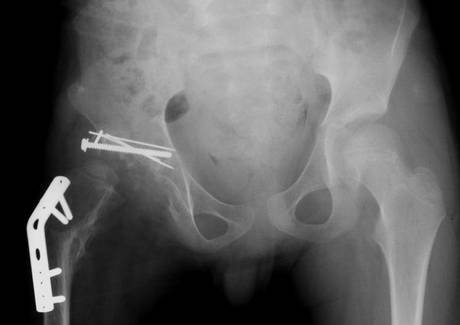

Ο Νορβηγός καλλιτέχνης Alexander Selvik Wengshoel ισχυρίζεται ότι έχει καταναλώσει το ισχίο του εις το όνομα της τέχνης...

Ο Wengshoel πήρε το μέρος του σώματος στο σπίτι έπειτα από χειρουργική επέμβαση αντικατάστασης ισχίου, και αφού το έβαλε στην κατσαρόλα προκειμένου να βράσει, το κατανάλωσε με πατάτες ογκρατέν και ένα ποτήρι κρασί.

Ο Wengshoel, που γεννήθηκε με παραμορφωμένο ισχίο και υπέστη σε πολλές αποτυχημένες επιχειρήσεις κατά την παιδική ηλικία, είχε περάσει το μεγαλύτερο μέρος της ζωής του σε μια αναπηρική καρέκλα ή με πατερίτσες πριν η ζωή του αλλάξει με υποστεί στη χειρουργική επέμβαση που του άλλαξε τη ζωή, σε ηλικία 21 ετών.